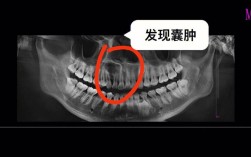

- 原理: 当根管治疗失败或无法进行时(例如根管钙化、器械折断在根管内、根尖有较大囊肿或肉芽肿、根管解剖形态复杂导致根管治疗难以彻底清创),可以考虑进行根尖手术,手术在牙龈上做一个切口,翻开牙龈瓣,暴露牙根尖,刮除感染的组织(如肉芽肿、囊肿),并切除一小段感染的牙根尖端(约3mm),然后对根尖断面进行倒充填(用特殊材料封闭根尖孔)。